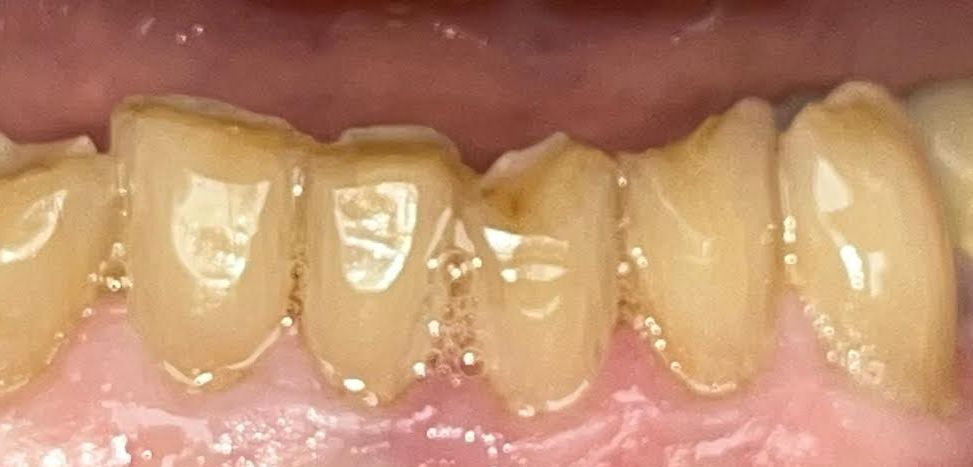

Dental Crowns Treatment

The patient had breakdown on his bottom teeth from grinding. We placed Zirconia crowns to improve the esthetics and function of the teeth.